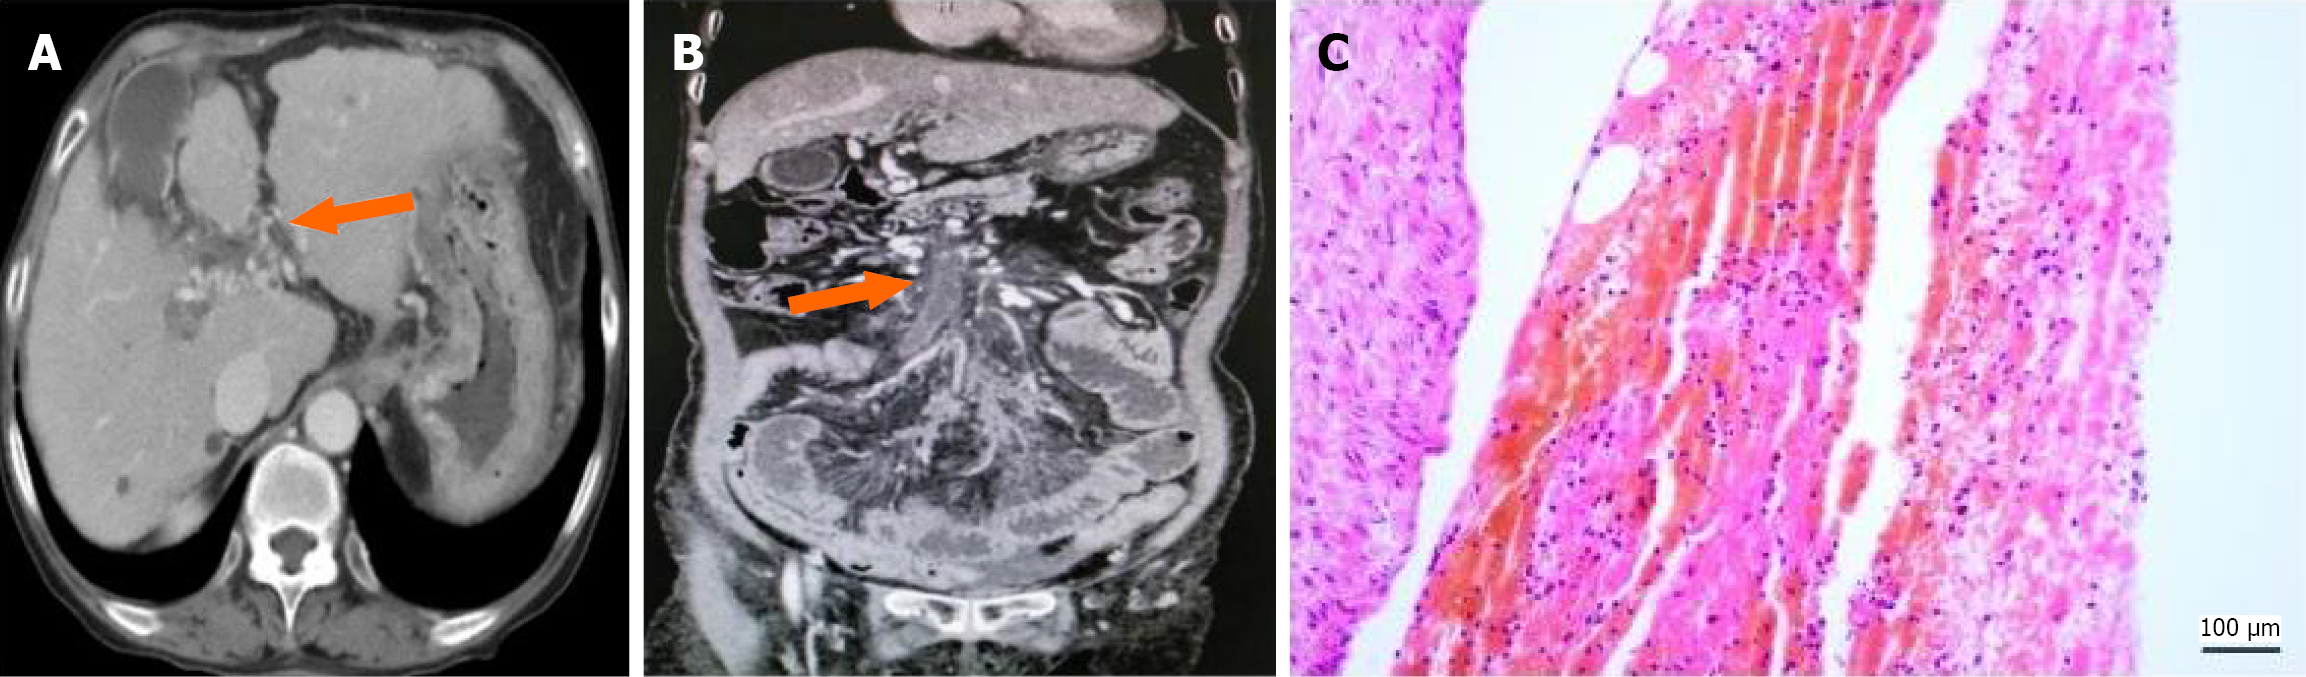

Chronic PVT: In 59 patients (34.5%), enhanced imaging revealed somewhat low-density thrombus shadows consistent with vascular anatomy, with either uniform or uneven density (CT value: 52.83 ± 9.84 HU), numerous collateral vessels forming around the thrombus, and thickened vessel walls (1.99 ± 0.46 mm) (Figure 3A).

Chronic PVT was found in 34 patients (26 underwent TIPS; 4 underwent percutaneous transhepatic portal vein access; 2 underwent surgical procedures; 2 underwent liver transplantation). The pathological composition mainly included platelets, red blood cells, and fibrous tissue, with thickened vascular walls and proliferation of surrounding small vessels. Figure 3B and C shows HE stained sections demonstrating alternating aggregation of red blood cells and fibrin, along with a thickened vascular wall.